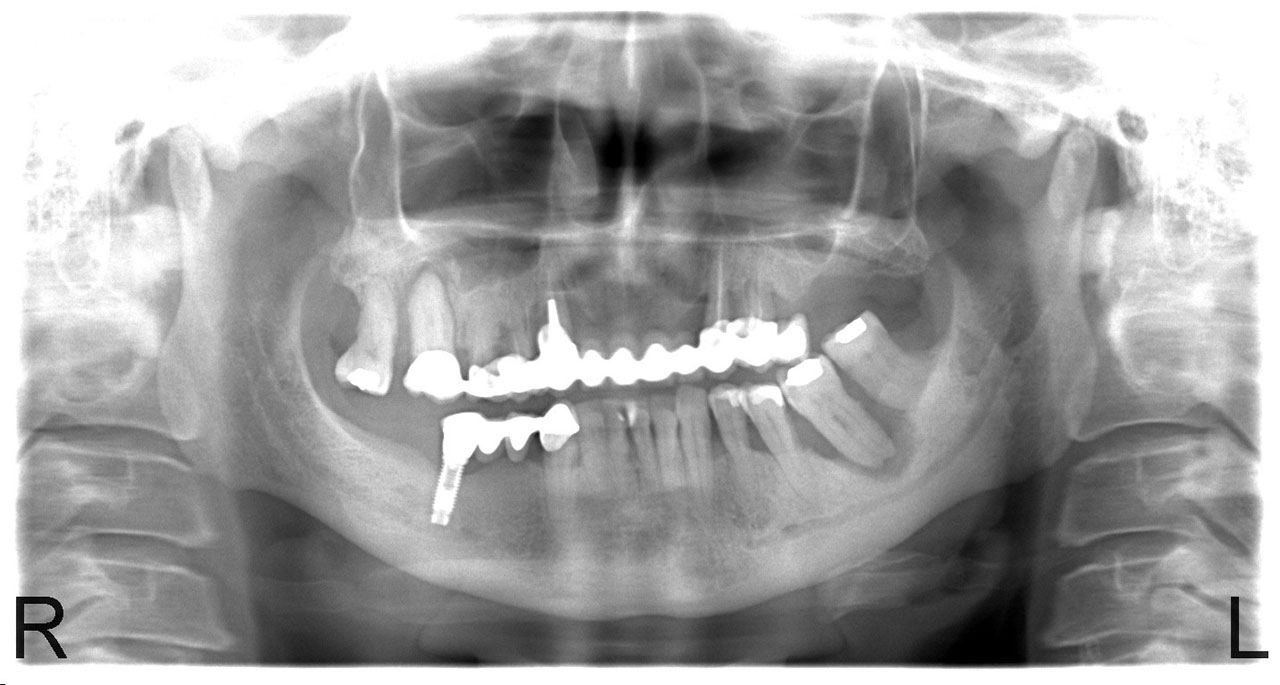

• esettanulmany-01

Implantáció előtt, gyulladt, törött fogak.

• esettanulmany-03

Imlantáció után,bal oldalon már a végleges hidakkal, jobb oldalon még csak az implantátumok.

• esettanulmany-04

Impantáció előtt, súlyos fogágy pusztulás, gyulladás látható.